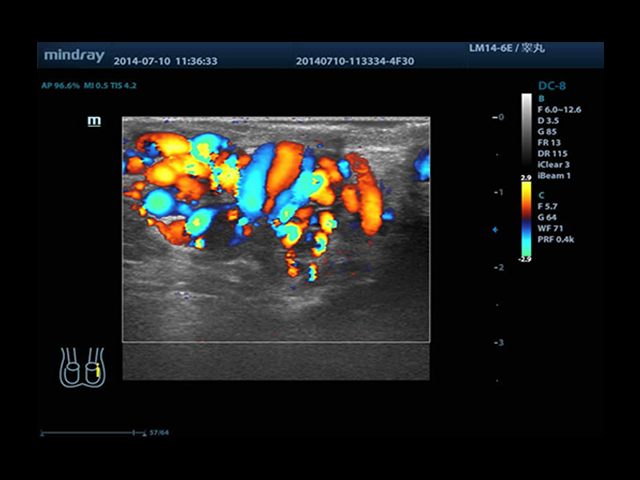

Mindray DC-8 Exp оснащен новым поколением датчиков с увеличенным количеством элементов и инновационной технологией "3T". Это позволяет достичь высокой детализации и качества изображения. Благодаря новейшей технологии iFlow, можно визуализировать даже самые мелкие сосуды и кровеносные пути.

• HR-flow™ - режим отображения кровотока с высоким временным и пространственным разрешением для точной и однородной визуализации сосудов, в том числе самых мелких

• Высокочастотный линейный датчик 38 мм Mindray l14-6NE

• Линейный датчик Mindray L14-6WE